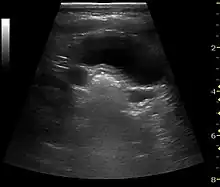

Figure 7. Advanced polycystic kidney disease with multiple cysts.[1]